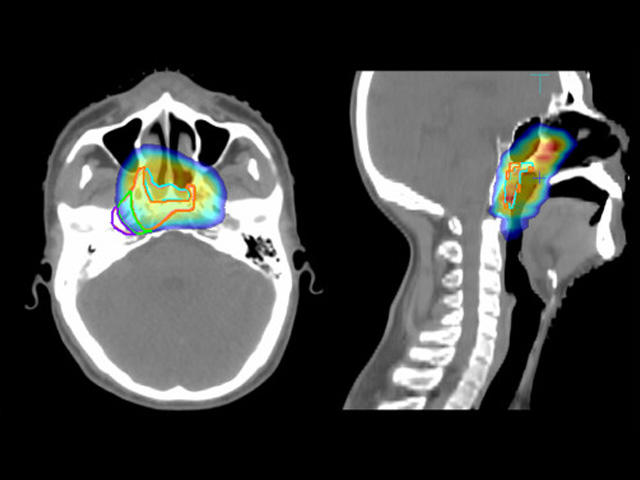

Imágenes diagnósticas de un carcinoma de nasofaringe con dosis de radiación presentadas en diferentes colores.

Imágenes diagnósticas de una persona con un carcinoma de nasofaringe que volvió (recidivante), en las que se destacan las distintas dosis de radiación recibidas durante el tratamiento anterior. El toripalimab es ahora el primer medicamento aprobado por la FDA para tratar el carcinoma de nasofaringe recidivante.

Fuente: Radiation Oncology. Marzo de 2014. doi: 10.1186/1748-717X-9-87. CC BY 2.0 DEED.